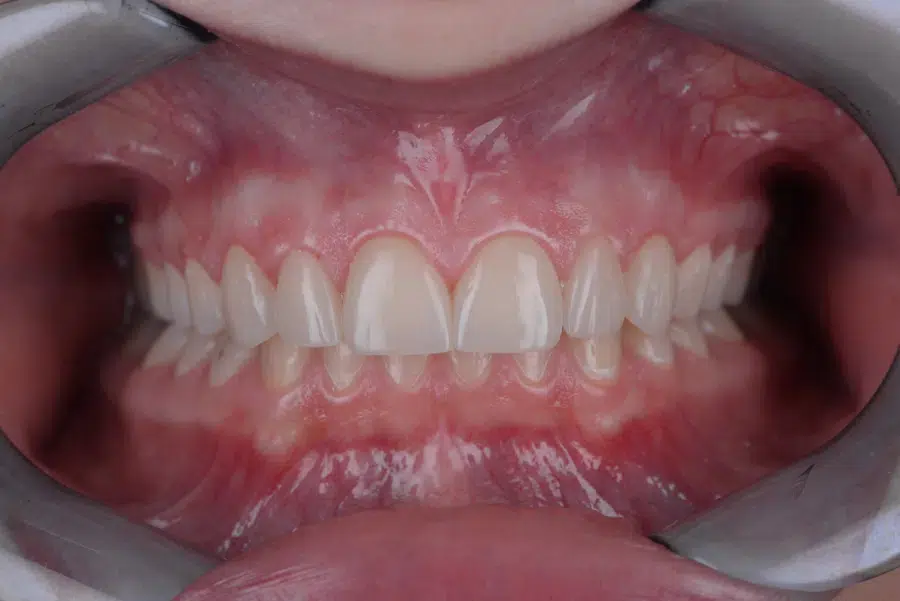

Caz de estetică dentară – Coroane ceramică presată E-Max

Provocarea acestui caz a fost tratarea minim invazivă a dinților restanți, în urma înlocuirii coroanelor vechi și obținerea unor dinți cu un volum mai mare pentru echilibrarea zâmbetului într-un aspect cat se poate de natural.

Pacientă a beneficiat de corecție gingivală cu laser pentru uniformizarea asimetriilor gingivale, tratamente endodontice de canal sub microscop, obturațiile vechi (plombe) schimbate cu materiale de compozit cu particule nanoceramice, și fațete dentare din ceramică presată E-Max.

Termen de finalizare 2 săptămâni de la amprentarea finală.